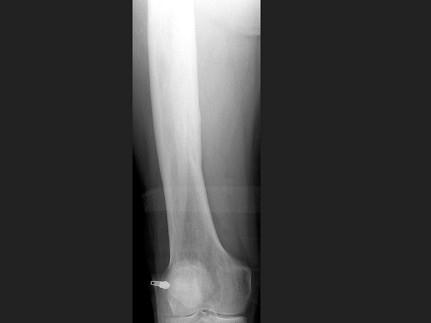

问题 男,67岁,右侧股骨痛,结合图像,最可能的诊断是?(?)

选项 A.骨纤维结构不良 B.维生素D缺乏病 C.成骨不全 D.软骨发育不全 E.畸形性骨炎

答案 E